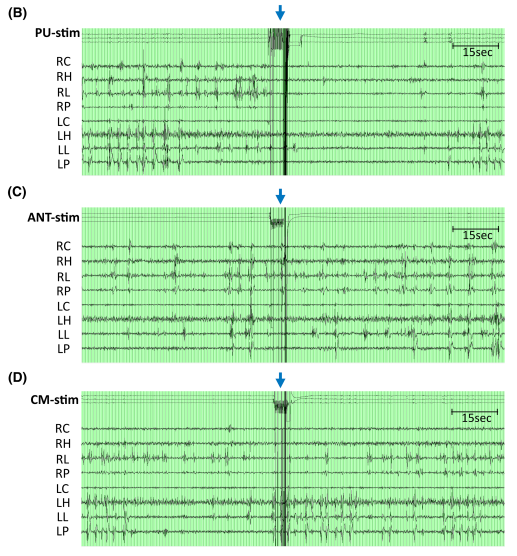

在一例接受SEEG植入以定位致癇區(qū)(EZ)的藥物難治性癲癇(DRE)患者中,深部電極(SEEG)被植入至三個(gè)丘腦區(qū)域(枕核[PU]、中央中核[CM]和前核[ANT])。對(duì)不同丘腦核團(tuán)進(jìn)行直接電刺激(DES),并同步采集了SEEG皮層接觸點(diǎn)的電信號(hào)。本報(bào)告中,我們采用1Hz、50Hz和100Hz的刺激頻率以區(qū)分低頻與高頻刺激效應(yīng)。然而,內(nèi)特斯尼高力SEEG適配的腦電檢測(cè)儀僅支持最高100Hz的刺激頻率輸出。因此,作者通過(guò)100Hz刺激模擬145Hz刺激的影響(假設(shè)50Hz刺激未觀察到副作用)。每個(gè)丘腦靶點(diǎn)的DES試驗(yàn)間隔至少2小時(shí)。每次試驗(yàn)包含以下參數(shù)組合: 1) 50Hz:脈寬300μs,電流強(qiáng)度1–2mA,電荷密度6–12μC/cm2,持續(xù)時(shí)間4s; 2) 100Hz:脈寬300μs,電流強(qiáng)度1–2mA,電荷密度6–12μC/cm2,持續(xù)時(shí)間4s; 3) 1Hz:脈寬1000μs,電流強(qiáng)度1–2mA,電荷密度20–40μC/cm2,持續(xù)時(shí)間30s。 每次不同參數(shù)和觸點(diǎn)刺激之間至少間隔2分鐘。分析區(qū)域包括:舌回、頂下小葉、海馬體頭部及中央前回下部。共獲取46次刺激試驗(yàn)的368組記錄,涵蓋兩種刺激強(qiáng)度、三種頻率、雙側(cè)刺激(左/右)及四個(gè)丘腦位點(diǎn)(ANT、CM、內(nèi)側(cè)和外側(cè)PU)。采用AnyWave軟件的Delphos算法自動(dòng)檢測(cè)IEDs,其敏感性>80%,特異性接近100%。通過(guò)計(jì)數(shù)ANT、CM和PU每次刺激后30秒及60秒內(nèi)的IEDs,并與刺激前30分鐘的基線IEDs對(duì)比,計(jì)算IED變化率: (刺激后的IEDs數(shù)量 /基線IEDs數(shù)量– 1) ×100。(IED減少≥33%為顯著降低) 并且對(duì)相關(guān)文獻(xiàn)進(jìn)行綜述研究:依據(jù)PRISMA-ScR指南,在MEDLINE和Embase數(shù)據(jù)庫(kù)中檢索關(guān)鍵詞組合“PU, ?stimulation, ?and ?epilepsy ”和“ PU and electrical stimulation”,限定英語(yǔ)文獻(xiàn)及人體研究。排除實(shí)驗(yàn)性研究、生理學(xué)研究、磁刺激研究、僅關(guān)注PU以外的其他丘腦核團(tuán)或未提供原始數(shù)據(jù)(如綜述類)的文獻(xiàn)。從符合納入標(biāo)準(zhǔn)的文獻(xiàn)中提取患者特征、癲癇病因、致癇區(qū)、干預(yù)參數(shù)及預(yù)后數(shù)據(jù)。

(1)病例介紹? 患者為32歲男性,自5歲起患DRE,合并Dandy-Walker綜合征、注意力缺陷多動(dòng)障礙、全面性發(fā)育遲緩。視頻腦電顯示雙側(cè)獨(dú)立起源的多發(fā)性癲癇發(fā)作(局灶性意識(shí)障礙性發(fā)作),發(fā)作起始于雙側(cè)中央顳-頂區(qū)及顳頂枕區(qū),伴行為停滯,且未因逐漸減量抗癲癇藥物(ASMs)而改變發(fā)作模式。6種抗癲癇藥物聯(lián)合迷走神經(jīng)刺激術(shù)可控制繼發(fā)性全面性強(qiáng)直陣攣發(fā)作,但患者每周仍出現(xiàn)2-3次行為停滯。磁共振成像(MRI)顯示廣泛雙側(cè)(右側(cè)較左側(cè)更顯著)灰質(zhì)異位合并多小腦回畸形,累及顳頂枕區(qū)。為確認(rèn)雙側(cè)顳頂枕區(qū)癲癇發(fā)作起始區(qū)(EZs),并探索腦深部電刺激術(shù)(DBS)或反應(yīng)性神經(jīng)刺激術(shù)(RNS)的潛在丘腦靶點(diǎn),行立體定向腦電圖(SEEG)檢查。61次發(fā)作期數(shù)據(jù)顯示雙側(cè)顳頂枕區(qū)多發(fā)致癇灶。給予不同參數(shù)的丘腦核團(tuán)電刺激以尋找目標(biāo)刺激靶點(diǎn)及評(píng)估刺激耐受性。 (2)刺激后IED變化 刺激后30秒IED(發(fā)作間期癲癇樣放電)減少率顯著高于60秒(30秒vs.60秒:199/368 vs.158/368,p=0.003)??傮w而言,三個(gè)丘腦核團(tuán)刺激后雙側(cè)后象限區(qū)域的IED減少最為顯著,其中枕核刺激效果最佳。50Hz與100Hz刺激的IED減少率顯著高于1Hz刺激?;颊呶磮?bào)告任何刺激相關(guān)副作用(≤2mA,40μC/cm2)。 (3)術(shù)后臨床隨訪 根據(jù)SEEG植入后電刺激結(jié)果,患者在枕核(PU)處植入閉環(huán)神經(jīng)刺激電極(RNS)。治療后2年達(dá)到Engel IIB級(jí)預(yù)后(電流1.8 mA、頻率125 Hz、脈寬160μs、電荷密度0.9μC/cm2、刺激時(shí)長(zhǎng)3s),發(fā)作頻率減少>75%,抗癲癇藥物(ASMs)從6種減至5種?;颊咦允鲂g(shù)后未再因癲癇缺勤,且術(shù)后2年成功完成為期2周的歐洲背包旅行(術(shù)前無(wú)法實(shí)現(xiàn))。 (4)文獻(xiàn)綜述 在235篇文獻(xiàn)中,共納入3項(xiàng)研究(12例患者)。10例患者刺激側(cè)與致癇區(qū)同側(cè),2例為雙側(cè)刺激。所有研究均采用>100Hz頻率刺激。在8例顳葉內(nèi)側(cè)癲癇患者中,6例通過(guò)內(nèi)側(cè)枕核刺激減少發(fā)作頻率,減輕發(fā)作嚴(yán)重程度。3例涉及后象限區(qū)域藥物難治性癲癇患者接受了枕核聯(lián)合皮質(zhì)RNS后,發(fā)作頻率均減少≥50%。 結(jié)語(yǔ)